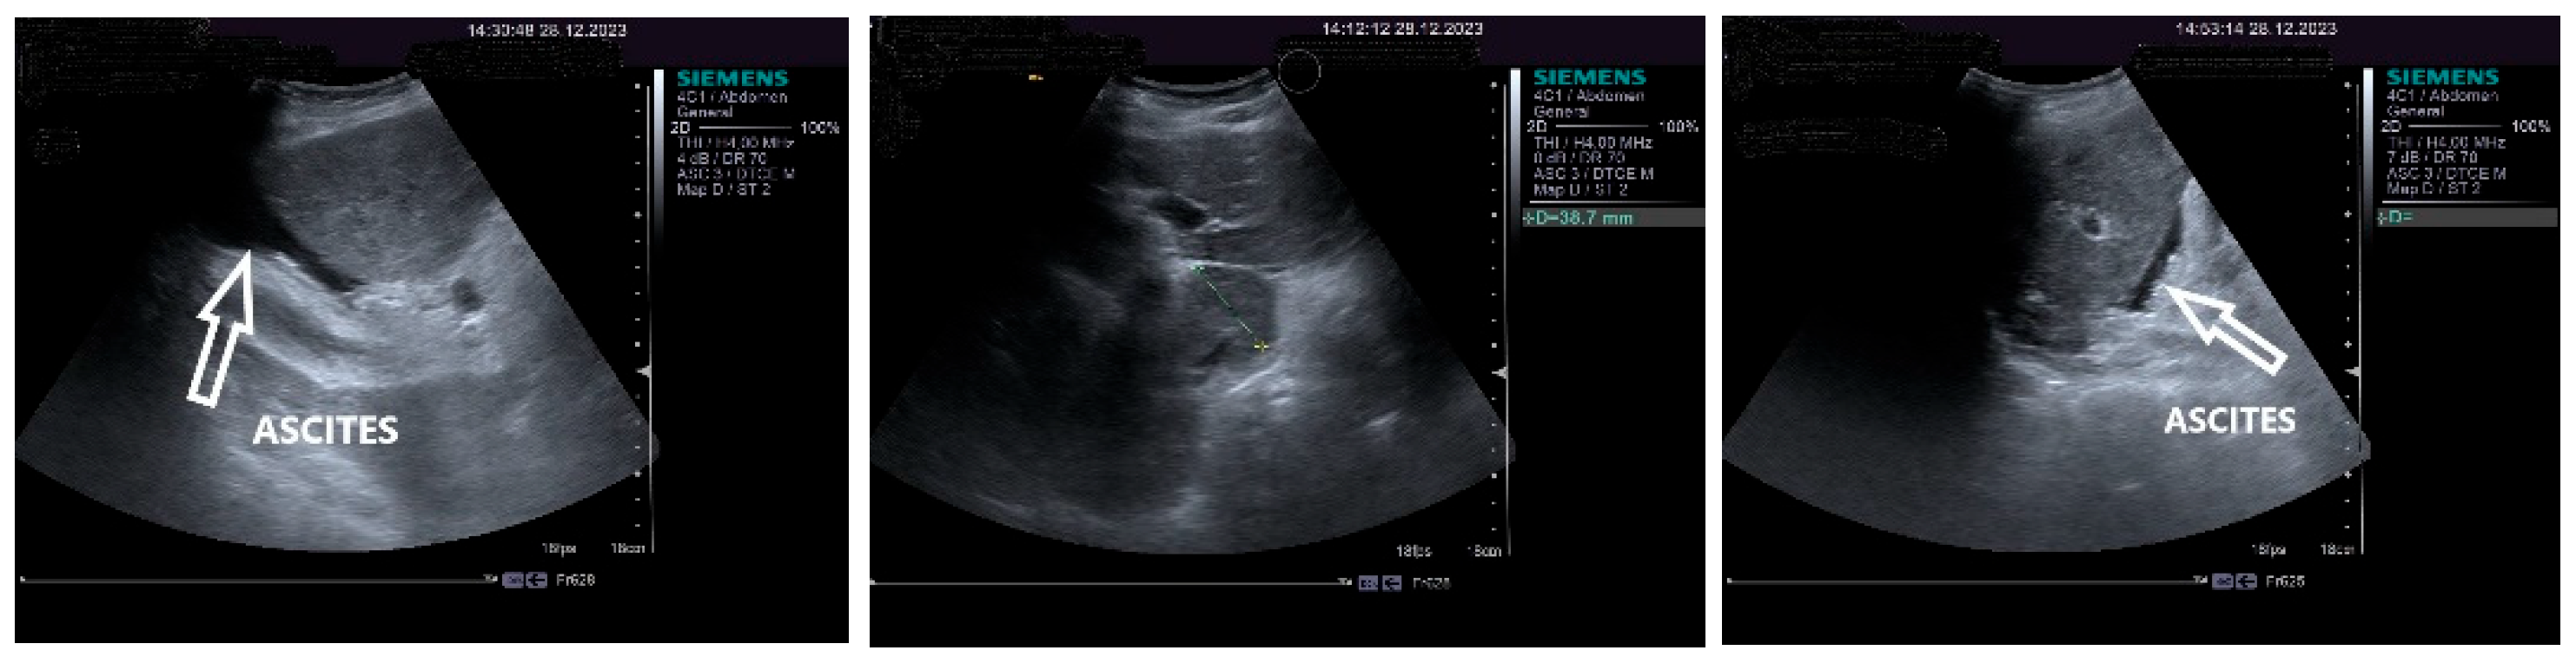

On physical examination, a mild tenderness of the right upper abdominal quadrant, a firm hepatomegaly, a palpable inferior pole of the spleen and a slight increase in abdomen volume were found. No other liver stigmata were noticed. The abdominal duplex ultrasound examination, performed with Siemens high-resolution equipment, showed hepatomegaly with a discrete irregularity of the liver surface, heterogeneity of the liver texture, the caudate lobe at the upper limit, filiform hepatic veins, massive thickening of the gallbladder wall, ascites in small quantity and mild splenomegaly with turbulence of the venous flow in the hilum. The question about liver cirrhosis was asked. Various aspects of the 2D ultrasound examination of the liver are depicted in Figure 2.

The pulsed Doppler ultrasound revealed a patency of the main portal vein as well as of the left and right portal branches and decreased, demodulated hepatopetal portal venous flow, with mildly decreased respiratory variability in the amplitude of the portal vein flow. The Dopler aspects of the liver and spleen are illustrated in Figure 4.

An important role in the imaging diagnostic approach of SOS/VOD is played by ultrasonography. According to some studies, it seems that ascites and gallbladder wall edema represent independent predictors in SOS/VOD diagnosis. Some authors reported that the thickness of the gallbladder wall correlated well with the HVPG. This particular aspect of the markedly thickened GB wall was also observed in the presented patient, associated with ascites and increase in the HVPG. Pulsed Doppler ultrasound is also useful for suggesting SOS/VOD, based on the study of the venous portal flow, which can be decreased or reversed. A significant increase in the HARI may also be associated with liver injury. Hepatic and portal flow anomalies revealed by duplex examination seem to correlate with the HVPG. However, as we have also noted, the reversed portal venous flow is not always recorded and, therefore, one cannot exclude SOS/VOD based on the absence of the hepatofugal portal flow sign [28]. The patient that we have presented in this case report displayed no reversed portal venous flow, but increased values of the HARI.

Figure 2. The 2D ultrasound aspect of the liver: perihepatic ascites (right,left), caudate lobe at the upper limit (middle).

Figure 4. Doppler examination. Liver: pulsed Doppler of the portal vein (left). Spleen: color Doppler of splenic vein (right).